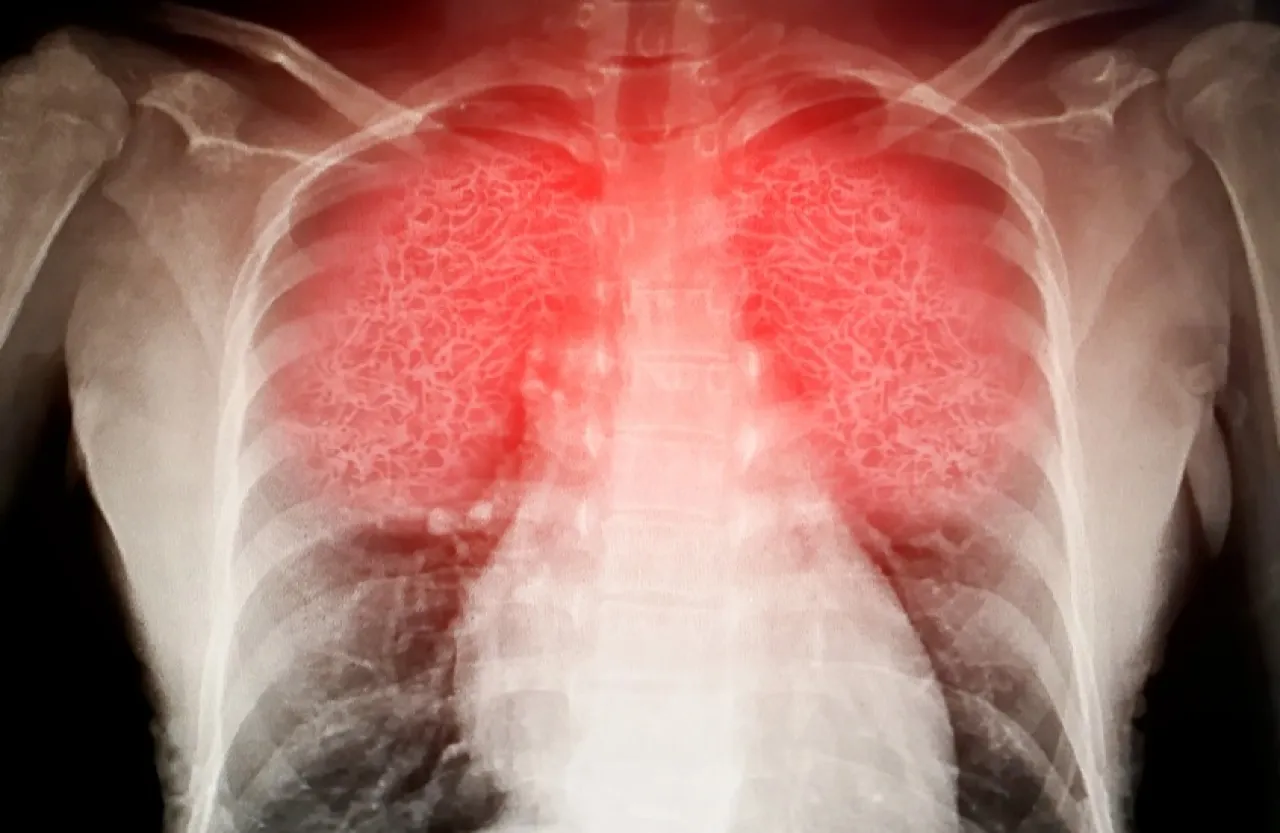

لكن دراسة حديثة حذّرت من أن هذا النشاط قد ينطوي على مخاطر صحية خفية، بعدما اكتشف باحثون نمساويون أن البيئة التي يُمارس فيها قد تحتوي على ملوثات كيميائية ضارة ناتجة عن الأحذية الخاصة المستخدمة فيه، ما قد يؤدي إلى مشاكل تنفسية خطيرة.

وكشف فريق البحث في جامعة فيينا أن أحذية التسلق المستخدمة في الصالات الرياضية المغلقة تطلق أبخرة كيميائية خطرة في الهواء، تحتوي على مركّبات سامة ترتبط بأمراض تنفسية مزمنة وتلف في الأعضاء، بل وبعض أنواع السرطان.

وأرجع الباحثون الخطر إلى النعال المطاطية لأحذية التسلق، والتي تحتوي على مواد مشابهة لتلك المستخدمة في صناعة إطارات السيارات، مثل مركب 6PPD-quinone، المعروف بتسببه في التهابات رئوية وتلف واسع في الأعضاء الحيوية، بحسب تجارب سابقة على الحيوانات. كما تم رصد مادة البنزوثيازول، التي ارتبطت بزيادة احتمالات الإصابة بسرطان المثانة بين العمال الصناعيين.